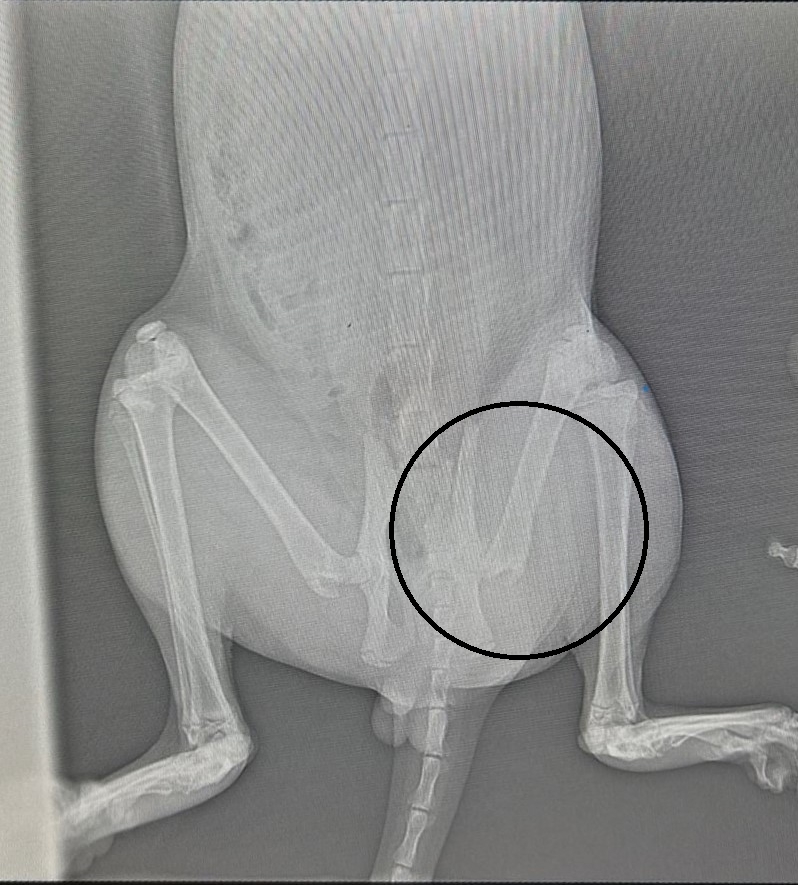

К Ивану Васильевичу на прием попал кот Зевс. Питомец выпрыгнул из окна и повредил лапу. Сразу же после инцидента ответственные владельцы обратились в нашу клинику. Где по рентген - исследованию питомцу был поставлен диагноз - перелом шейки бедра ЛТК. Далее была планово проведена операция по резекции шейки бедра. После чего Зевс вернулся к своему обычному образу жизни. И снова пользуется лапой в полной мере. Больше информации об этом клин. случае по ссылке https://vk.com/wall-232218233_22 . . . На ортопедический прием к Ивану Васильевичу можно записаться по номеру: +7-953-468-68-66 WhatsApp +7-953-468-68-66